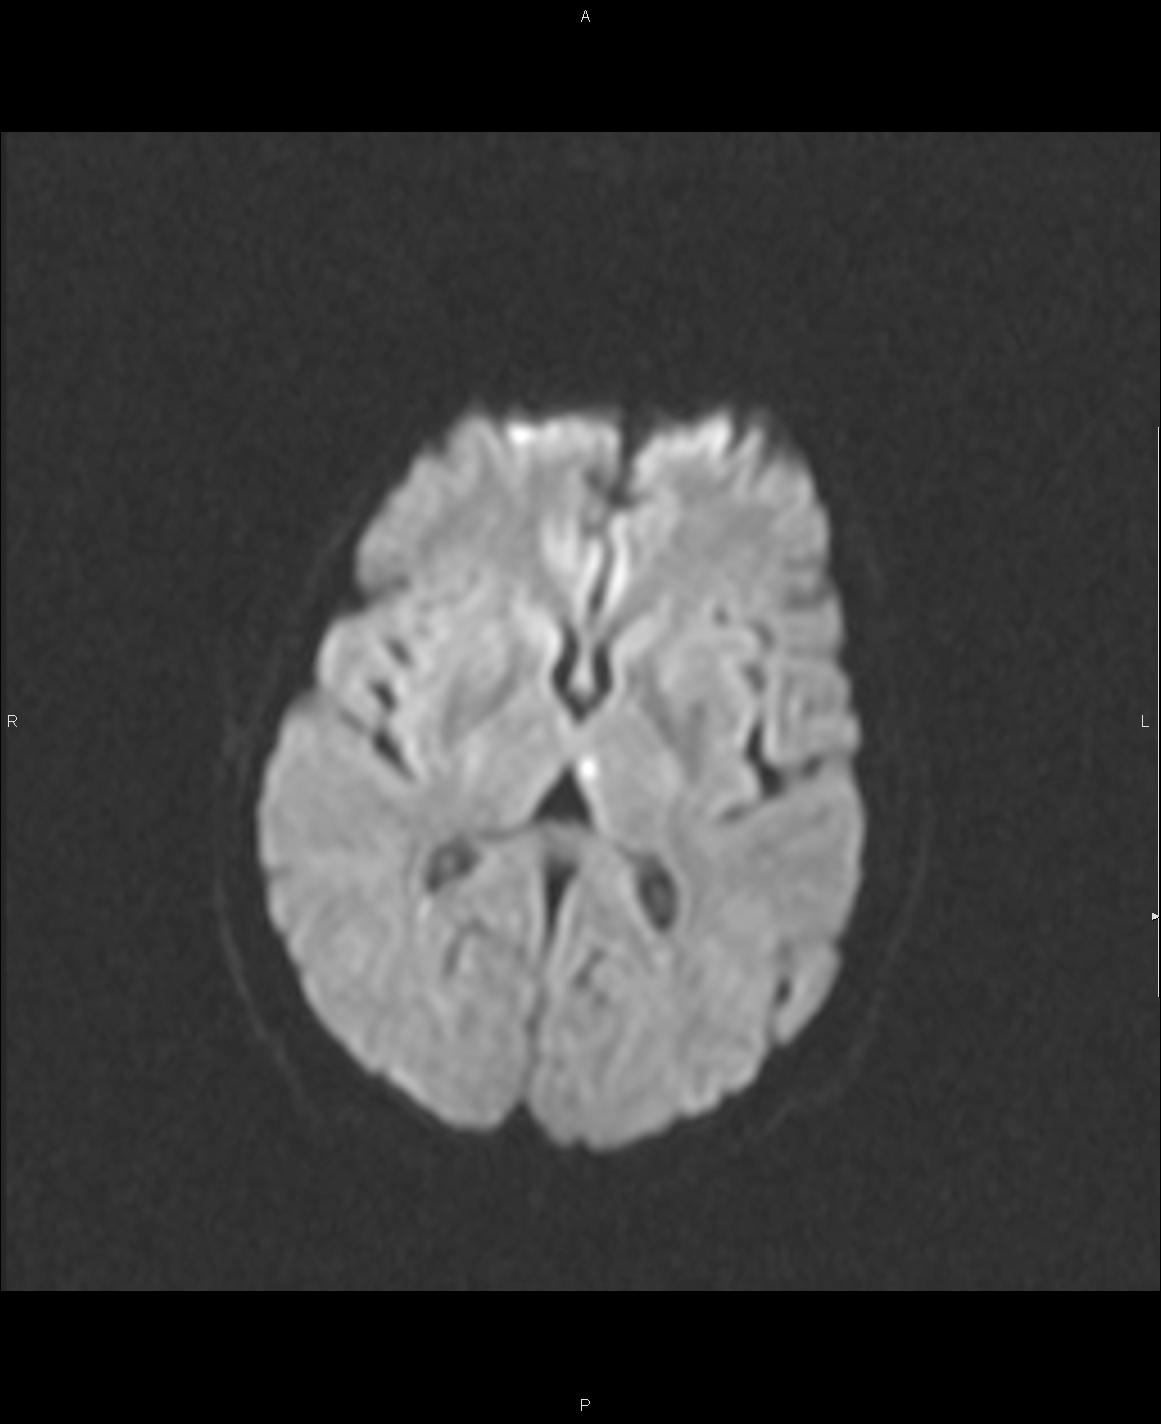

sesión de casos miércoles 6 de marzo 2013 BFR ( IPP)

Paciente con disminución de fuerza en hemicuerpo  derecho y  disminución del nivel de conciencia. TC de cráneo normal.